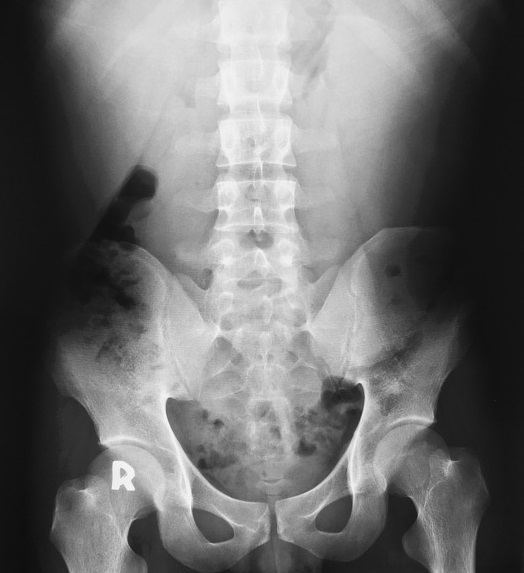

Aspect radiologique de la

cirrhose du foie sur cliche ASP de face est

image de hypertrophie du foie ( hepatomegalie ) et

de splenomegalie . |